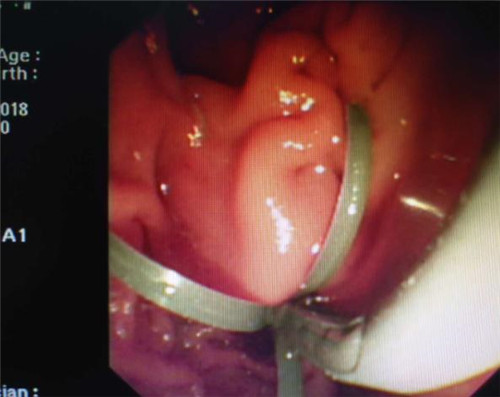

经过多个科室的配合,在介入科X线机下,曹鹏医生于十二指肠镜下顺利将导丝插入患者胆管内,注入二氧化碳气体造影,X线下见患者肝内外胆管扩张,胆管末端明显有占位性病变,患者胆管末端因肿瘤压迫,非常狭窄,经过多级扩张后,顺利为患者置入胆道支架。手术非常顺利,患者生命体征平稳,大家都松了口气。